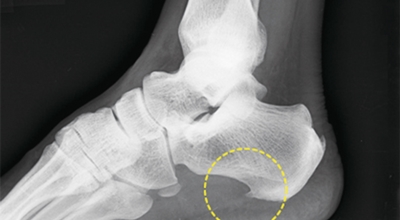

족저 근막이란 발가락 시작지점부터 발뒤꿈치뼈까지 발바닥 전체를 감싸고 있는 두꺼운 막을 말해요. 족저 근막은 발바닥 아치를 지속시켜 발바닥이 지면을 내딛음으로써 나타나는 충격을 흡수하는 중요한 역할을 수행하고 있어요. 이 족저 근막에 일차적으로 서서히 조직 손상이 일어나고 계속적인 활동으로 인해 염증이 커지면서 발 뒤꿈치 부근 통증을 유발하게 되는데 염증은 무리하고 반복적인 동작, 과도한 사용으로 마찰에 의해 발생해요.

주요 증상은 통증으로 발뒤꿈치 안쪽이 아주 아프며, 맨발로 바닥을 걸을 때 걸음을 내딛을 때마다 통증이 있어요. 가장 심한 통증은 아침에 일어나 첫 걸음을 뗄 때인데, 밤에 족저근막이 수축하다가 발에 체중이 가해지면서 갑자기 늘어나는 현상입니다.